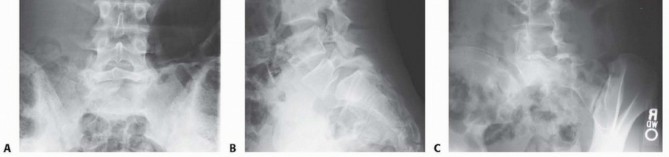

Initial imaging includes standing posteroanterior and lateral radiographs of the spine ( FIG 3A,B ). Oblique views ( FIG 3C )

may provide additional information in certain cases, but their use for diagnosing spondylolysis without listhesis in adolescents is controversial.1

FIG 3 • Posteroanterior (PA) (A), lateral (B), and oblique (C) radiographs demonstrating high-grade spondylolisthesis.

(continued)

FIG 3

•

Axial (

D

) and sagittal (

E

) CT scan sections demonstrating bony deformity.

F.

MRI demonstrating high-grade spondylolisthesis.

Plain radiographs are used to establish the overall alignment of the spine in both the coronal and sagittal plane. The sagittal alignment should be noted, particularly the degree of lumbar lordosis above the lumbosacral kyphosis. Any structural abnormalities in the spine in addition to the slip should be noted. These abnormalities

include the presence of spina bifida occulta, scoliosis, or sagittal plane abnormalities. Other spinal problems should be treated as per individual merits.

Computed tomography (CT) scans with three dimensional (3-D) reconstruction are valuable in defining the exact bony abnormality and will help in preoperative planning (

FIG 3D,E

).

Magnetic resonance imaging (MRI) studies are indicated when there is evidence of neurologic compromise. MRI provides good visualization of nerve roots, spinal stenosis, and cauda equina compression (

FIG 3F

*).